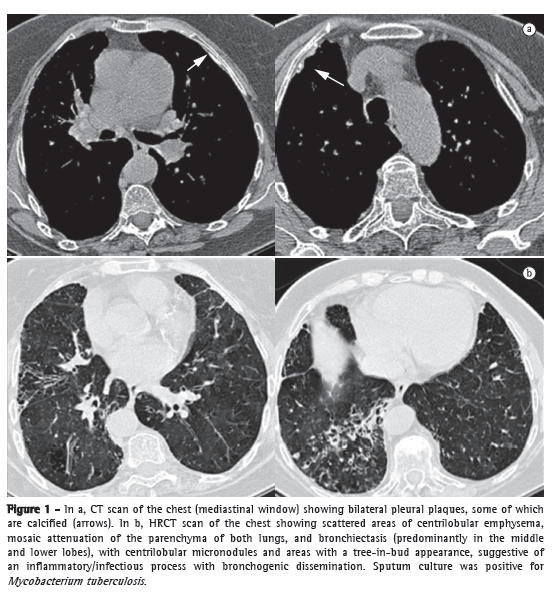

A HRCT scan of the chest revealed areas of centrilobular emphysema, bilateral mosaic attenuation, and bronchiectasis in the right upper lobe, as well as in the middle and lower lobes, in which there were also centrilobular micronodules and areas with a tree-in-bud pattern, suggestive of an inflammatory/infectious process with bronchogenic dissemination. The mediastinal window showed bilateral pleural plaques, some of which were calcified (Figure 1).

Sputum culture was positive for Mycobacterium tuberculosis. The patient was started on specific treatment, and, at this writing, she was under outpatient follow-up treatment.